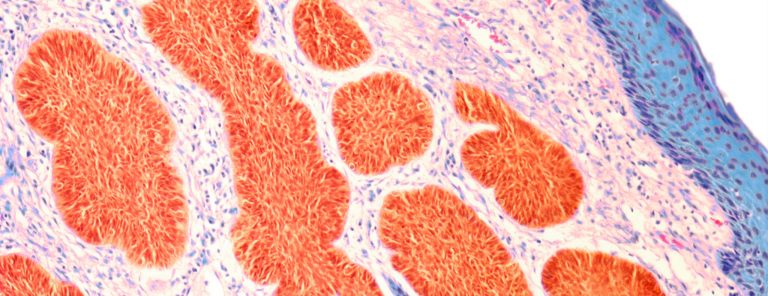

- العلقة: ذُكِرت كلمَةِ عَلق خمس مرّاتٍ فِي القرآن الكريم، وَهِيَ تَشبيه بقطعَةِ العلق كالدمِ الجامد أو كالدودة التي تَعيشُ فِي البِرَك والمُستنقعات، وَهُوَ أقرَبُ وَصفٍ لِطورِ الإنسان عِندَما تتكاثر الخلايا وَتنقَسِم لِتُصبِحَ عبارَة عَن كُتلَةٍ مِنَ الخلايا وَتَتَعَلّقُ بجدارِ الرّحِم، وَيبقَى هذا الطَور إلى اليوم الأربعين، وقال الله تعالى : ( ثُمَّ كَانَ عَلَقَةً فَخَلَقَ فَسَوَّى) القيامة:38، وما يُمَيّز العلقة أنّها تتكوّن مِن طبقتين خارجيّة (مُغَذية وآكلة)، وداخِليّة (وَهِيَ التي يَخلِقُ فِيها الله الإنسان).